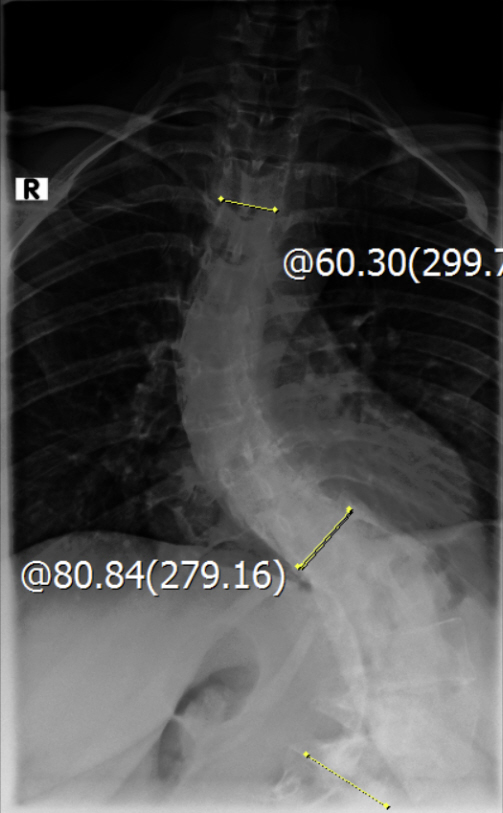

Thorakolumbalskoliose mit aktuellen COBB-Winkeln von 80 und 60 Grad...wenig Schmerzen und daher meistens glücklich

Viele kennen sich aus, daher möchte ich euch meine aktuellen Röntgenbilder nicht vorenthalten und hänge sie unten an.

Ich war beim MVZ Gersthofen, dort wurden die Röntgenbilder gemacht…die massive Verschlechterung war sehr offensichtlich

Dort wurden die Winkel gemessen, unten 80 Grad und oben 60 Grad…eine Verschlechterung von über 2 Grad pro Jahr, wenn man es auf die ganze Zeit berechnet

Die Winkel hab ich nachgemessen, wie der Arzt der Hessing und hier mal als Screenshot